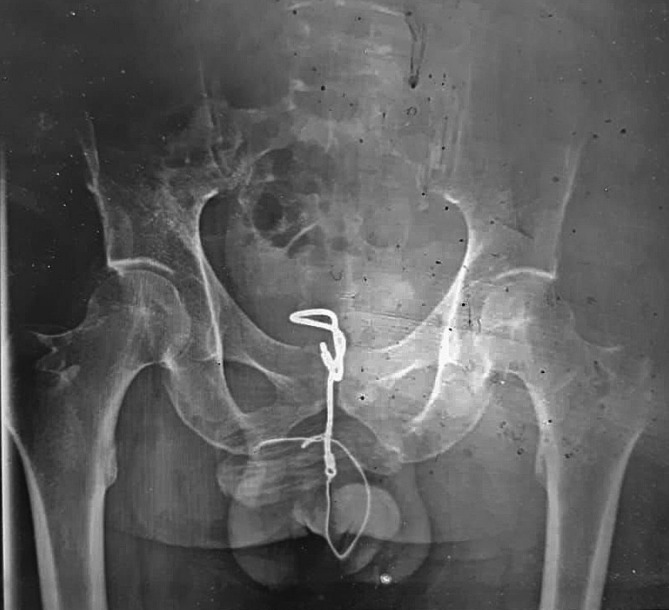

Case presentation: A 32-year-old man with no prior medical or psychiatric history presented with acute penile pain of three hours' duration. On examination, the patient remained calm, and a plastic cable was visibly protruding from the urethral meatus. A plain pelvic X-ray revealed a 9-cm radio-opaque foreign body along the urethral tract. After administering tetanus prophylaxis, the foreign bodies were successfully extracted under local anesthesia. Postoperatively, the patient experienced only mild urethrorrhagia and resumed normal urination. Given the unusual nature of the self-injurious behavior, a psychiatric evaluation was performed, which revealed an acute psychotic episode leading to a diagnosis of schizophrenia.